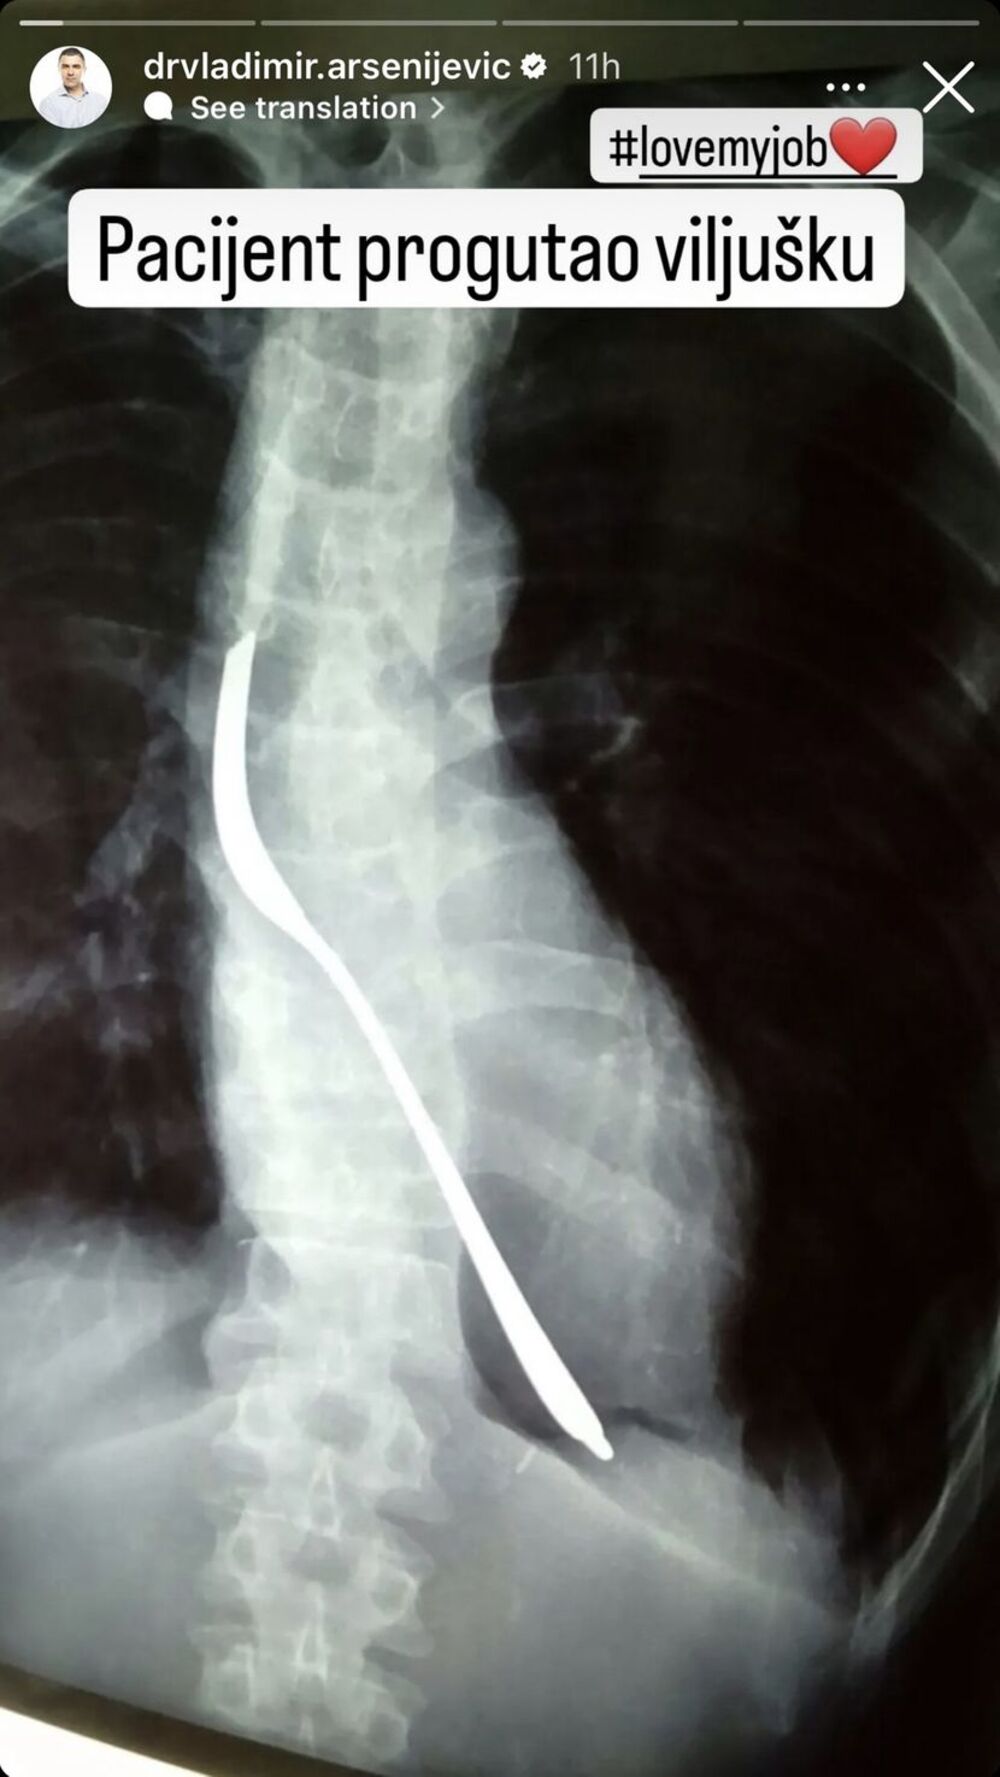

Naime, Vladimir Arsenijević, načelnik prijema u Urgentnom centru KC Srbije objavio je na svom Instagram nalogu rendgenski snimak pacijenta koji je progutao ni manje, ni više nego viljušku.

"Pacijent progutao viljušku. Ja volim moj posao", napisao je Arsenijević.

Pojedinosti o pacijentu nisu poznate i pretpostavlja se da će strano telo biti uklonjeno operativnim putem.